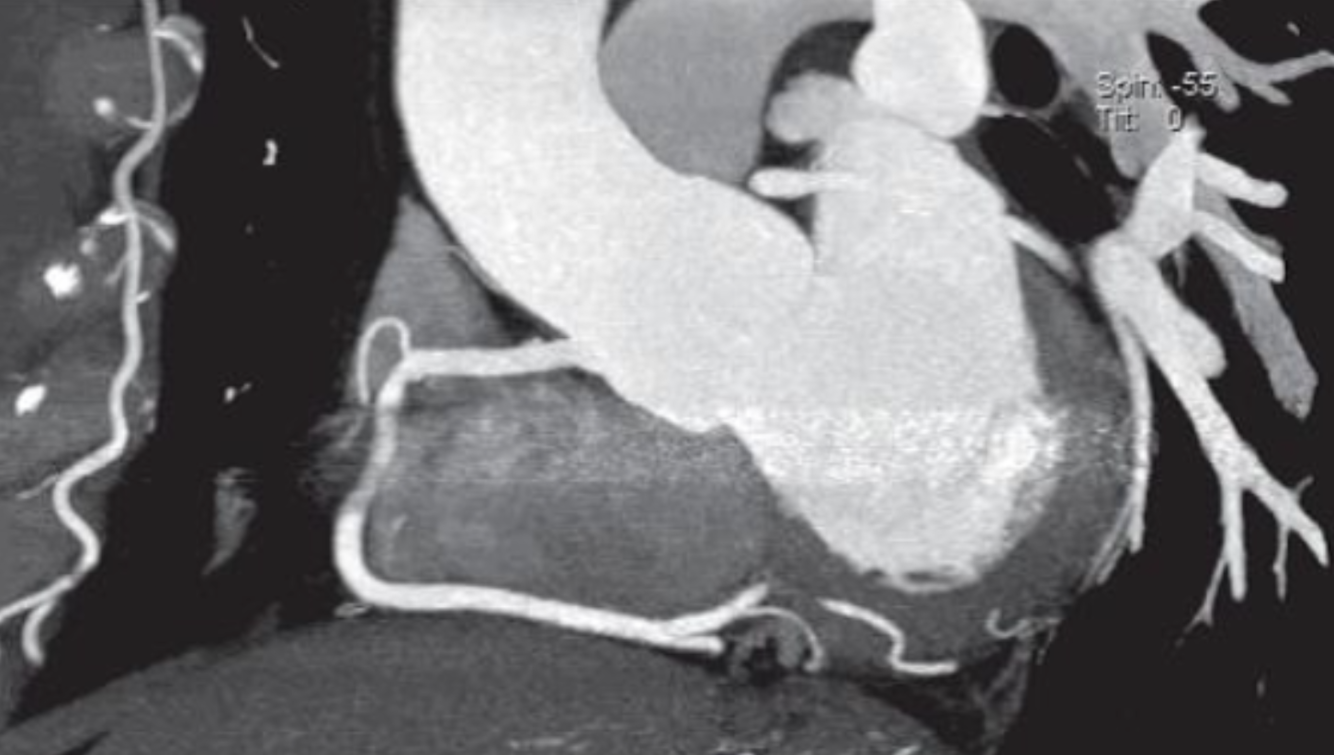

What type of post-processing methods were used to generate the reformatted image shown below?

Multiplanar reformatting and thin slab MIP (5 mm)

What is one major limitation of volume rendered images?

degree of stenosis cannot be determined by these images alone